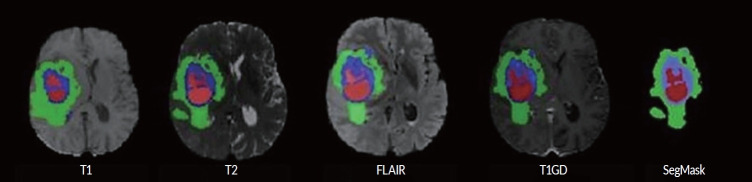

Methods: This study utilizes a support vector machine (SVM) classifier using radiomics features to predict the overall survival (OS) of GBM, IDH-wildtype patients to short (<12 months) and long (≥12 months) survivors. A dataset comprising multi-parametric magnetic resonance imaging scans from 574 patients was analyzed. Radiomic features were extracted from T1, T2, fluid-attenuated inversion recovery, and T1 with gadolinium (T1GD) sequences. Low variance features were removed, and recursive feature elimination was used to select the most informative features. The SVM model was trained using a k-fold cross-validation approach. Furthermore, clinical parameters such as age, gender, and MGMT (O6-methylguanine-DNA methyltransferase) promoter methylation status were integrated to enhance prediction accuracy.

Abstract Image